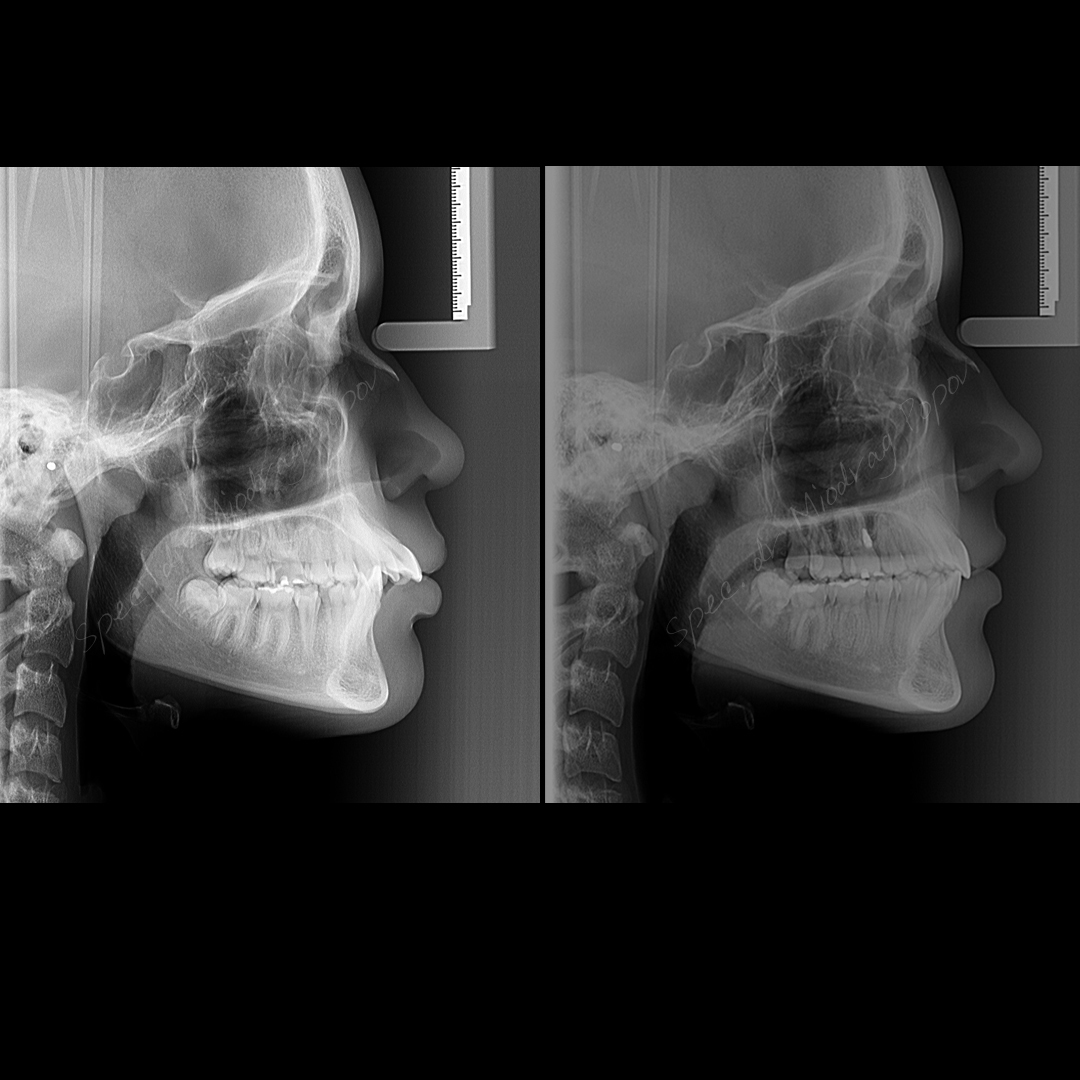

Slučaj ortodontske terapije II klase s vađenjem gornjih prvih predkutnjaka.

Tokom tretmana, svi prostori su zatvoreni, a profil lica transformisan.

Rezultat? Jasno definisana brada i harmoničan profil!